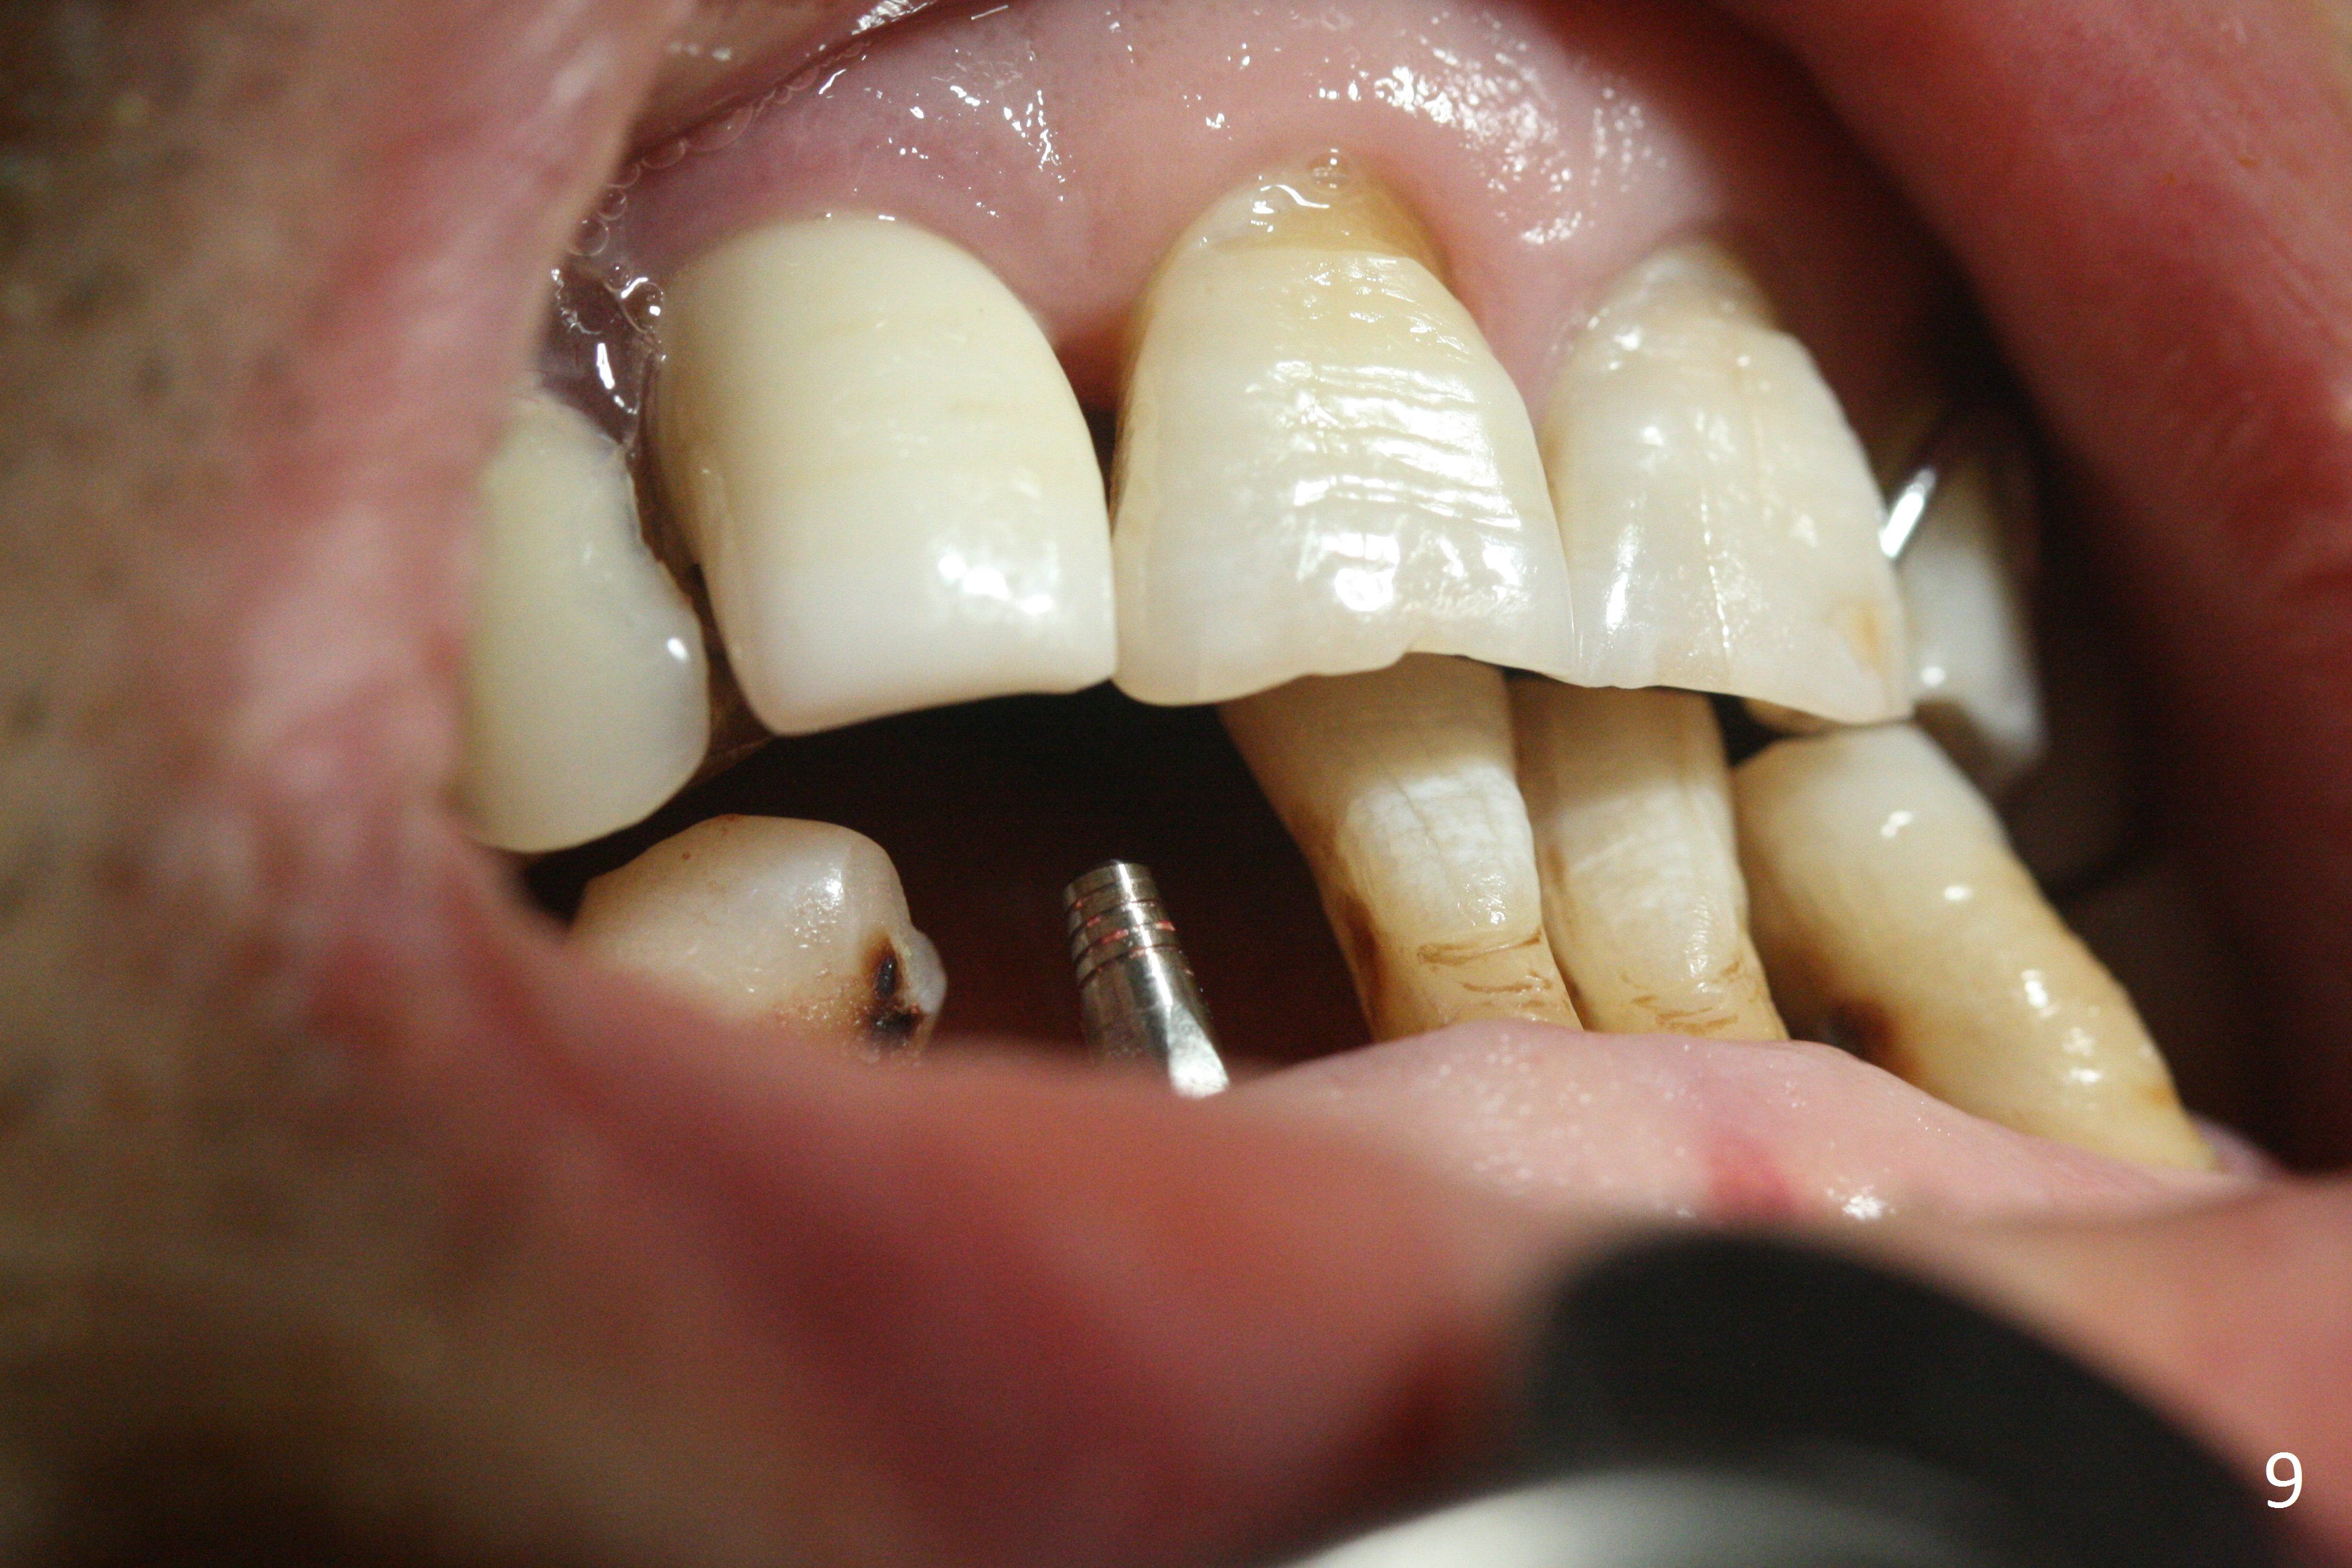

The lower dentition is special, consisting of a residual root (Fig.1 ^), 2 incisor (I), 1 canine (C), 1 premolar (P) and 1 molar (M). The residual root looks like an incisor with rotation of 90º (Fig.2,3). Osteotomy is initiated (Fig.4) for a 3x16(2) mm 1-piece implant (Fig.5 with 45 Ncm). The implant is being placed as distal as possible (Fig.4 arrow) so that a large canine-like provisional is to be fabricated in the large edentulous space (Fig.8,9) after bone graft (Fig.6,7 *). The gingiva around the provisional (Fig.10 P) remains healthy 11 days postop with occlusal clearance against the opposing dentition (Fig.11). The implant threads are not exposed with the help of bone graft 3 months 1 week postop (Fig.12). The gingiva around the implant is healthy (Fig.13). Soft tissue socket is formed by the provisional (Fig.14 *).